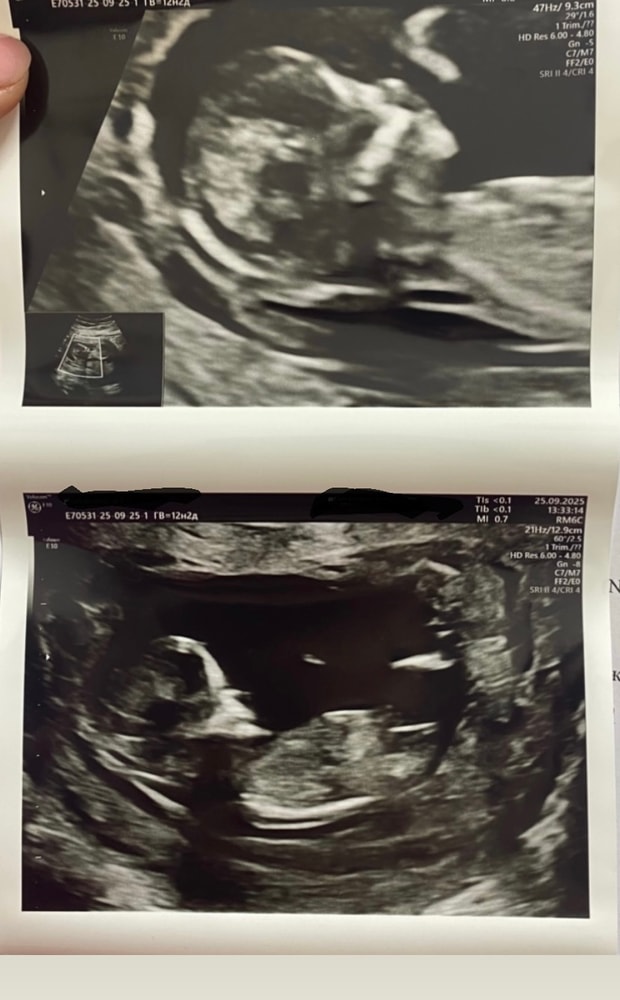

вчера вечером лежа на кровати впервые ощутила легкие копошения и толчки🥹🫣 Божечки, это так волнительно и трепетно было🥹 анализы плановые осмотры итп все хорошо🙌🏻 а так, конечно, я пошла бы на УЗИ в энный раз😝😂 но потерплю до 2 скрининга🫠 ой кстати давление у меня повышенное либо оно всегда было таким либо сейчас так стало с 🤰🤷♀️ вчера ку